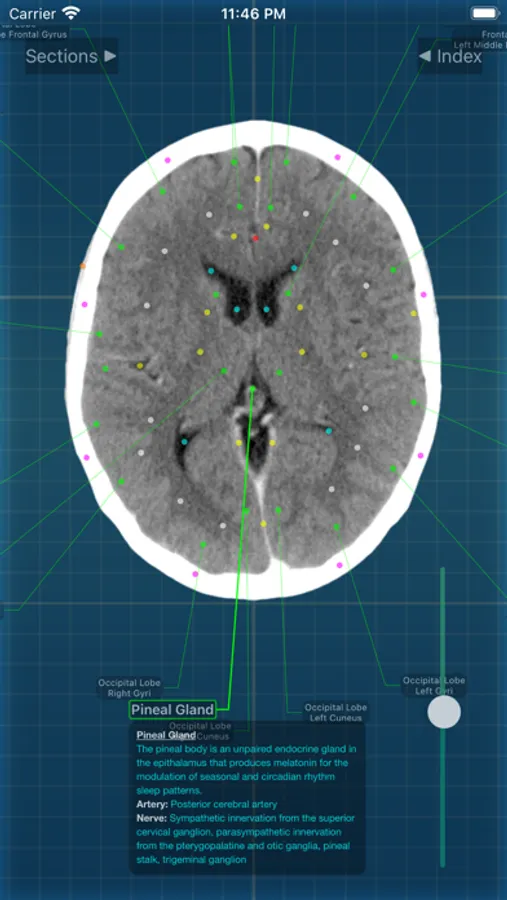

X-Anatomy is a transaxial cross-sectional human anatomy interactive medical imaging atlas using CT images, designed for medical professionals & all students of anatomy.

* Includes hundreds of images from actual human patient body scans.

* Detailed anatomic notes about muscles, vessels, and key anatomic structures

* Complete color-coded index of anatomic structures

* FOLLOW the positions and pathways of your selected anatomic structures automatically as you SCROLL through the image slices.